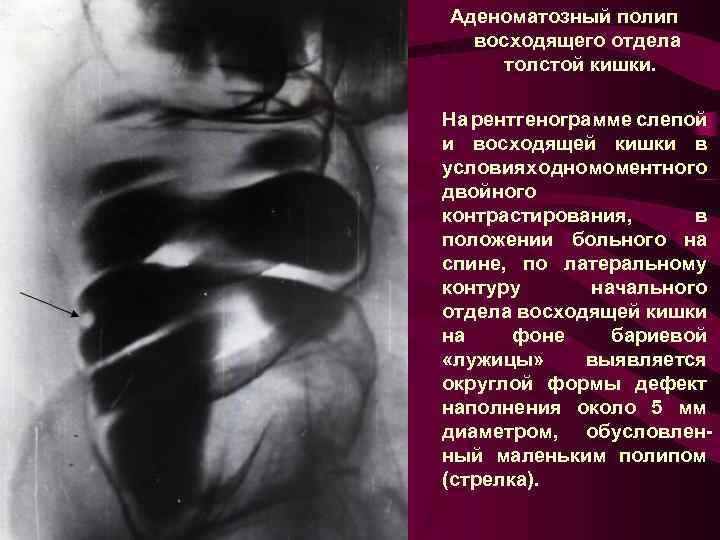

Аденоматозный полип восходящего отдела толстой кишки. На рентгенограмме слепой и восходящей кишки в условиях одномоментного двойного контрастирования, в положении больного на спине, по латеральному контуру начального отдела восходящей кишки на фоне бариевой «лужицы» выявляется округлой формы дефект наполнения около 5 мм диаметром, обусловленный маленьким полипом (стрелка).